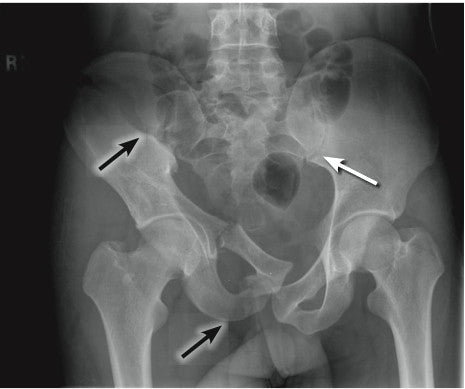

The pictures above and to the right should give you a good visual for these bones. One thing that you’ll notice is that these bones form one large boney ring, and two smaller, lower boney rings. While it might not seem like a stroke of genius, this is actually a crucial point when talking about fractures and trauma. When subjected to severe forces, these boney circles tend to break in not one, but two locations. This predilection to multiply break sites is one of the aggravating factors in pelvic trauma. We’ll talk more about this later, but keep it in mind.